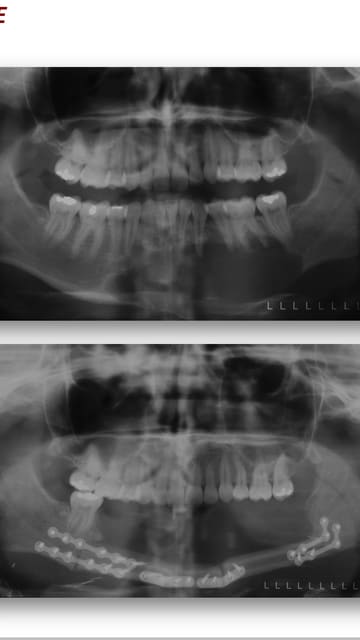

Je reçois ce patient en urgence, il consulte pour un abcès de la dent de sagesse 48, mais très vite je m'apercois que les signes sont bizarres: aucune douleur dentaire dans le secteur même 48, la voussure remonte très haut le long de la branche mandibulaire et elle n'est pas vraiment fluctuante comme dans un abcès. il présente un trismus associé. Le patient est très jeune (19 ans) et je le connais. (bien sûr!)

Je fais une pano pour voir et là l'horreur! a priori le nerf mandibulaire est récliné tout en bas de la mandibule et il ne semble subsister que les corticales osseuses!!!!

When it looks like "bubbles" and it goes into the ramus, it's probably an ameloblastoma, as said above.

Je penche + pour kerato. Le kyste dentigère ne semble plausible car image pas typique.

améloblastome polikystique hélas

Contrairement au titre de la discussion, je ne trouve pas cette image particulièrement inquiétante même si elle est impressionnante par son étendue.

L'améloblastome, en fait, c’est souvent le même tableau et la même image radiologique que le kyste dentigère ou le kératocyste, et c’est l’histologie qui tranchera.

Le traitement privilégié est la résection suffisante de l’os avec le kyste dès que le diagnostic est posé. En effet la simple énucléation occasionne 75 % de récidive. et radiothérapie si on retrouve des cellules tumorales lors de l'anapat des contours de la pièce.

Mon patient a rencontré ce jour le Pr Majoufre Lefèbvre, chirurgien Maxillo faciale à Bordeaux et comme le dit Canin plus haut ça ne l'a pas du tout inquiété! elle en voit tous les jours!!! (a priori c'est bien un améloblastome)

Elle propose l'avulsion de 48 avec un curetage du kyste puis de remonter a travers le kyste et d'effectuer un curetage par l'intérieur, tout ça en ambulatoire sur une journée. il y aura bien sur une biopsie pour évacuer tous risques cancéreux.

Je suis un peu perplexe! On se retrouve avec un os "creux"?? quid du risque de fracture?? du risque de récidive?? D'autant plus que le patient présente un trismus sévère, comment vont-ils procéder pour accéder au site?

Comme promis voila le cas dont je te parlais. Evidemment ça fait un peu peur et si pour ton patient la reconstruction peut être évitée ce sera surement beaucoup mieux pour la suite.

Dans ce cas ci, avec cette atteinte du rebord basilaire il n'y avait pas trop le choix je suppose.